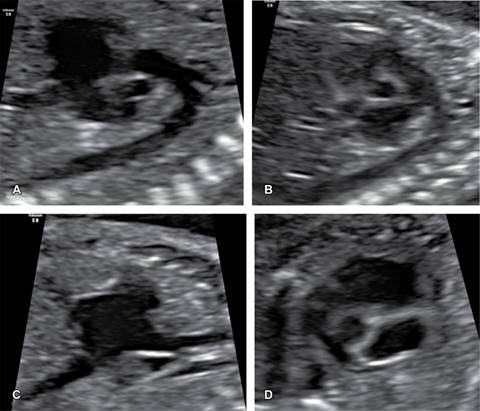

Abordaje integral

Ante el diagnóstico prenatal de una cardiopatía debe completarse el protocolo de estudio:

Evaluación anatómica fetal: en fetos con cardiopatía, se estima que 37% presenta anomalías extracardiacas.9

Asesoría genética y procedimiento invasivo: en este grupo de pacientes, 28% presenta anormalidades cromosómicas.9

Otros estudios: neurosonografía fetal, evaluación por infecciones (panel TORCH), autoanticuerpos SSA/SSB, evaluación por esclerosis tuberosa, etcétera. Evaluación de la curva de crecimiento fetal.

El manejo posterior al diagnóstico prenatal involucra un equipo multidisciplinario conformado por distintos especialistas: médico materno fetal, cardiólogo pediatra, obstetra, genetista perinatal, neonatólogo, psicólogo, cirujano fetal y cirujano pediatra.10 Este abordaje permite establecer el tiempo óptimo de nacimiento, sitio adecuado y manejo postnatal, las opciones terapéuticas disponibles y el pronóstico perinatal (Figura 4).